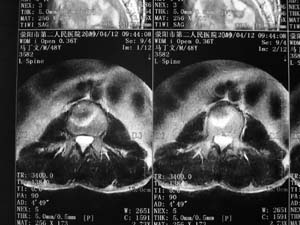

标题: MRI2131:男,腰痛三月向右下肢放射一月余 [打印本页]

标题: MRI2131:男,腰痛三月向右下肢放射一月余

骨质轻微破坏,硬化明显,椎管未见异常,考虑良性骨瘤的可能性大,

椎体增生 硬化 囊变。考虑:退变!

支持考虑退变,许莫结节形成

椎体前缘骨质增生硬化、囊变。椎旁软组织未见确切异常。考虑椎体前缘软骨结节。

1)l3椎体前上缘许莫氏结节形成。2)腰椎退行性改变。

l3椎体前上缘许氏结节。

退变,许莫氏结节.腰1椎体血管瘤.

l2大部分椎体信号增高-----脂肪变性,转移待排。l3 椎体t2 低信号考虑硬化增生。